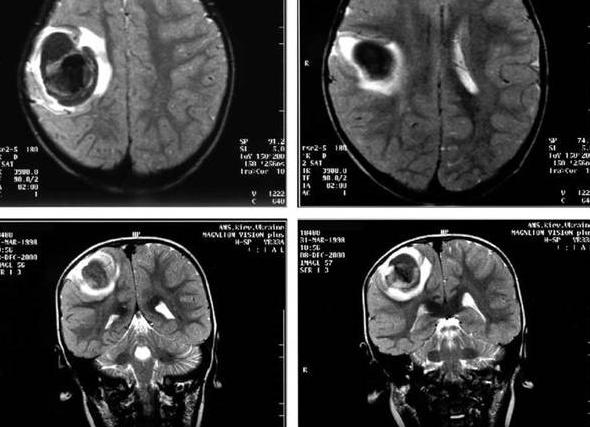

МРТ коленных суставов

Коленный сустав очень уязвим. Ему приходится выдерживать значительные динамические нагрузки. Болевой синдром в коленях беспокоит многих людей, но чаще всего с ним сталкиваются спортсмены и люди преклонного возраста. Иногда для выяснения причины появления болей и хромоты не обойтись без МРТ коленного сустава. Поэтому пациенты хотят знать, что такое МРТ коленного сустава и как его делают.